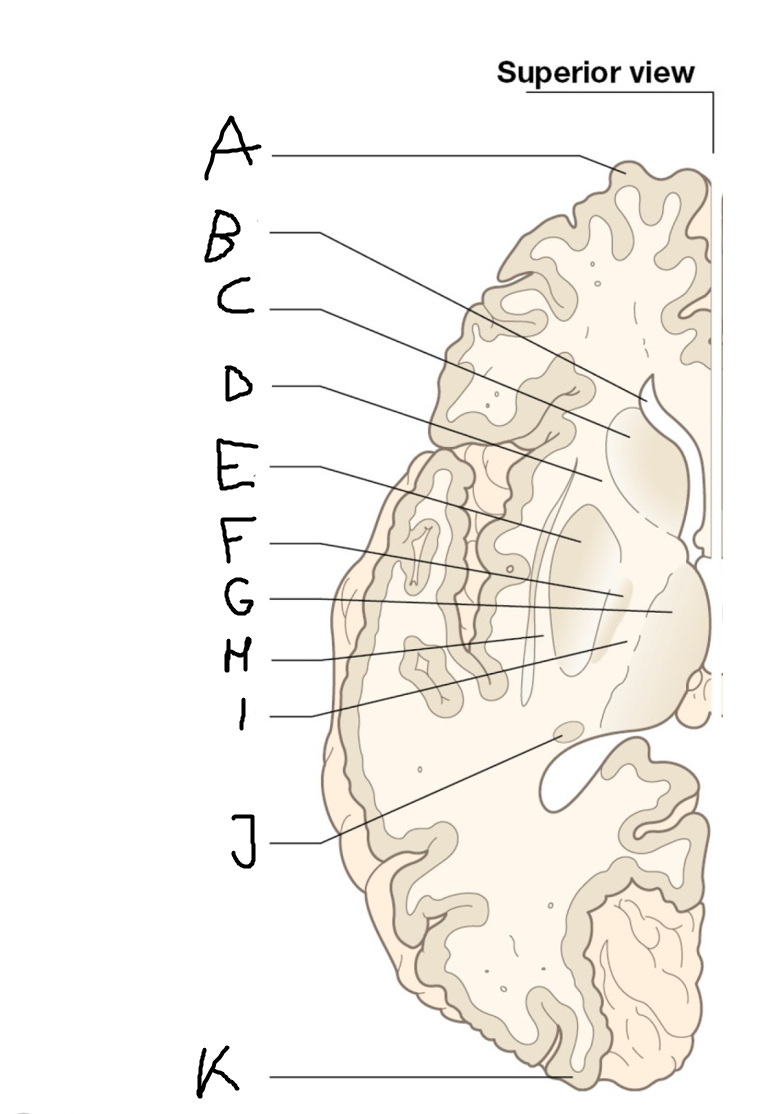

internal capsule (posterior limb)

B

anterior horn of lateral ventricle

C

head of caudate nucleus

D

internal capsule (anterior limb)

E

putamen

F

globus pallidus

G

Thalamus

H

External capsule

I

internal capsule (posterior limb)

J